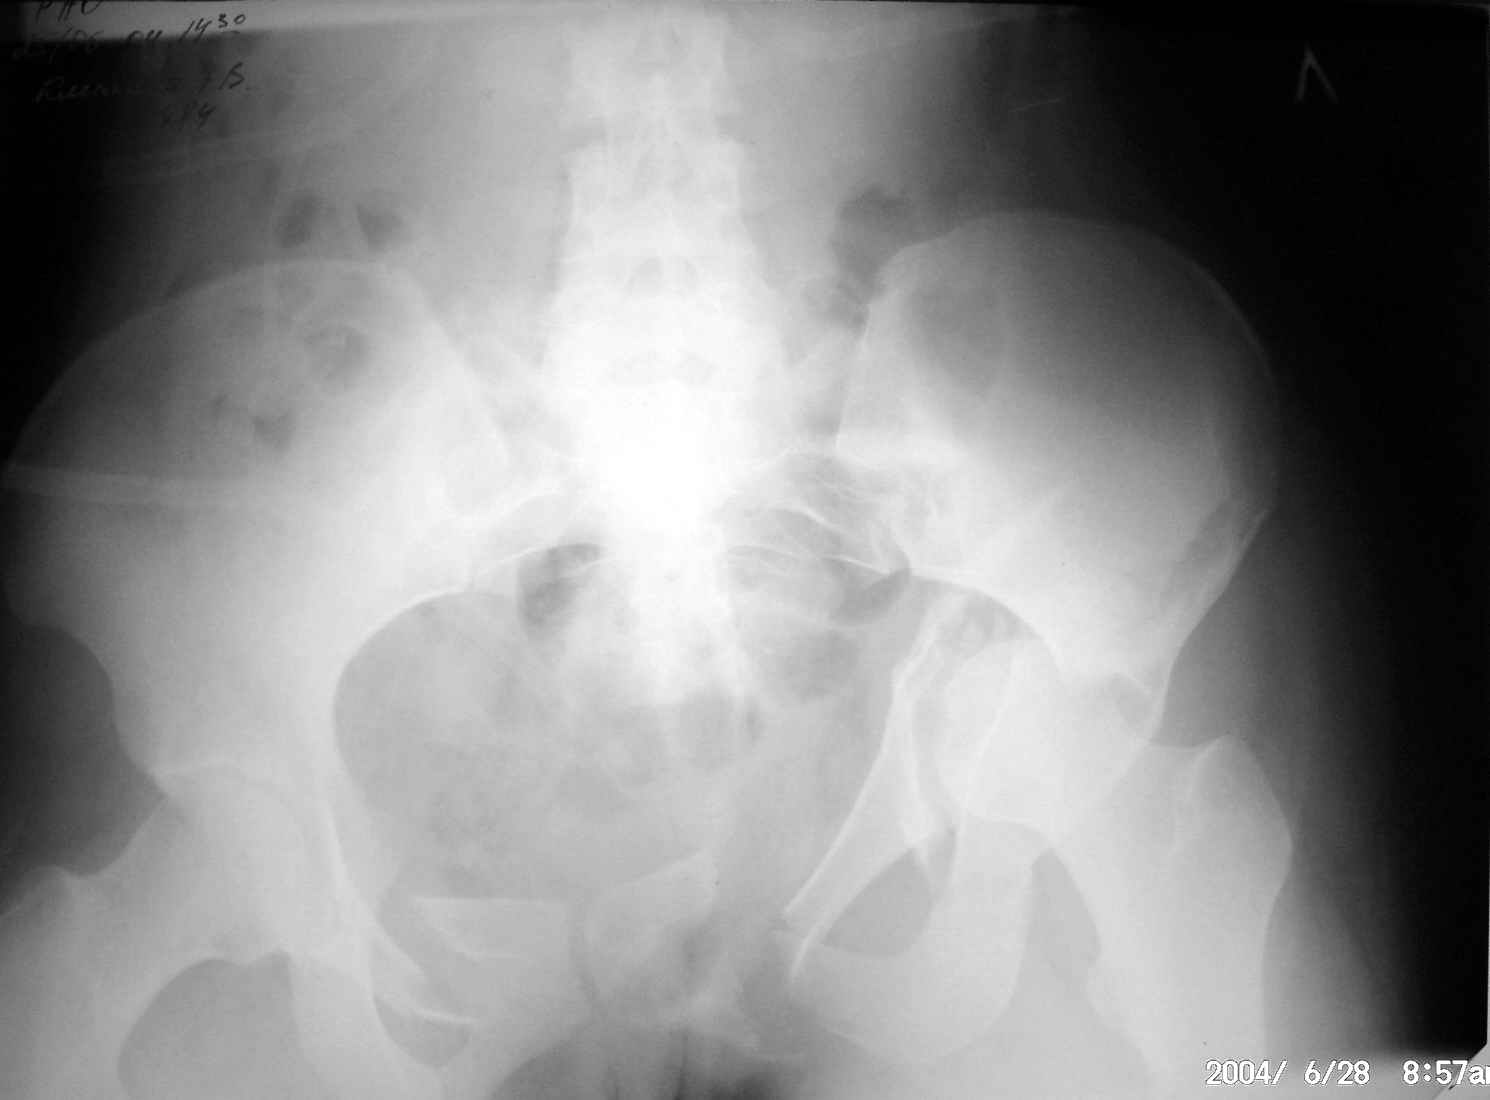

Травма таза

Дорогие коллеги, Посоветуйте, как лучше лечить пациентку с травмой таза после автоаварии? Пока нходится на вытяжении за обе ноги. В.П.Охлопков, Новоуральск.